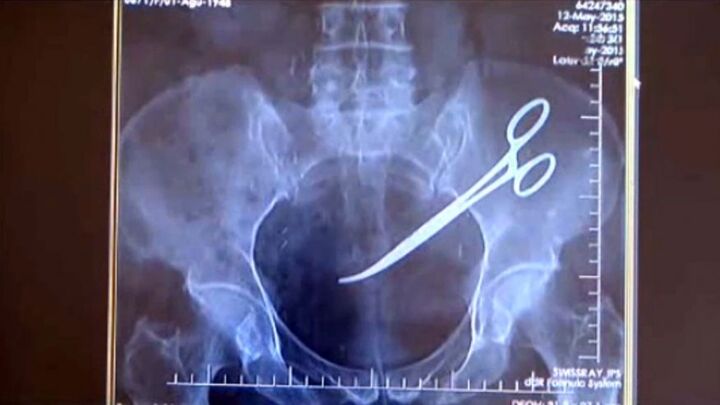

Như tin đã đưa trước đó, ngày 25/12, ông Ma Văn Nhật (54 tuổi, Bình Trung, Chợ Đồn, Bắc Kạn) đi khám tại BV Gang thép Thái Nguyên, bất ngờ phát hiện trong ổ bụng có một chiếc panh dài 15cm.

Bệnh nhân đã được phẫu thuật tại Bệnh viện Gang thép Thái Nguyên vào ngày 31/12/2016. Chiếc panh đã bị han gỉ, và đâm thủng đại tràng của bệnh nhân đã được bác sĩ lấy ra thành công.